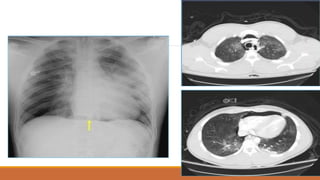

TDMP lượng ít

TDMP lượng vừa

TDMP lượng nhiều

PHIM THẲNG ĐỨNG

•TÙ GÓC SƯỜN HOÀNH

•BÓNG MỜ VÙNG THẤP XÓA BỜ VÒM HOÀNH VỚI

GIỚI HẠN TRÊN LÀ ĐƯỜNG CONG DAMOISEAU

•ĐẨY TRUNG THẤT VỀ PHÍA ĐỐIDIỆN

•XẸP PHỔI THỤ ĐỘNG (+/-)

•THAY ĐỔI THEO TƯ THẾ

TDMP TỰ DO

PHIM NGHIÊNG

•TÙ GÓC SƯỜN HOÀNH TRƯỚC VÀ SAU

•BÓNG MỜ VÙNG THẤP VỚI GIỚI HẠN TRÊN LÀ

ĐƯỜNG CONG LÕM XUỐNG DƯỚI

ĐƯỜNG CONG DAMOISEAU